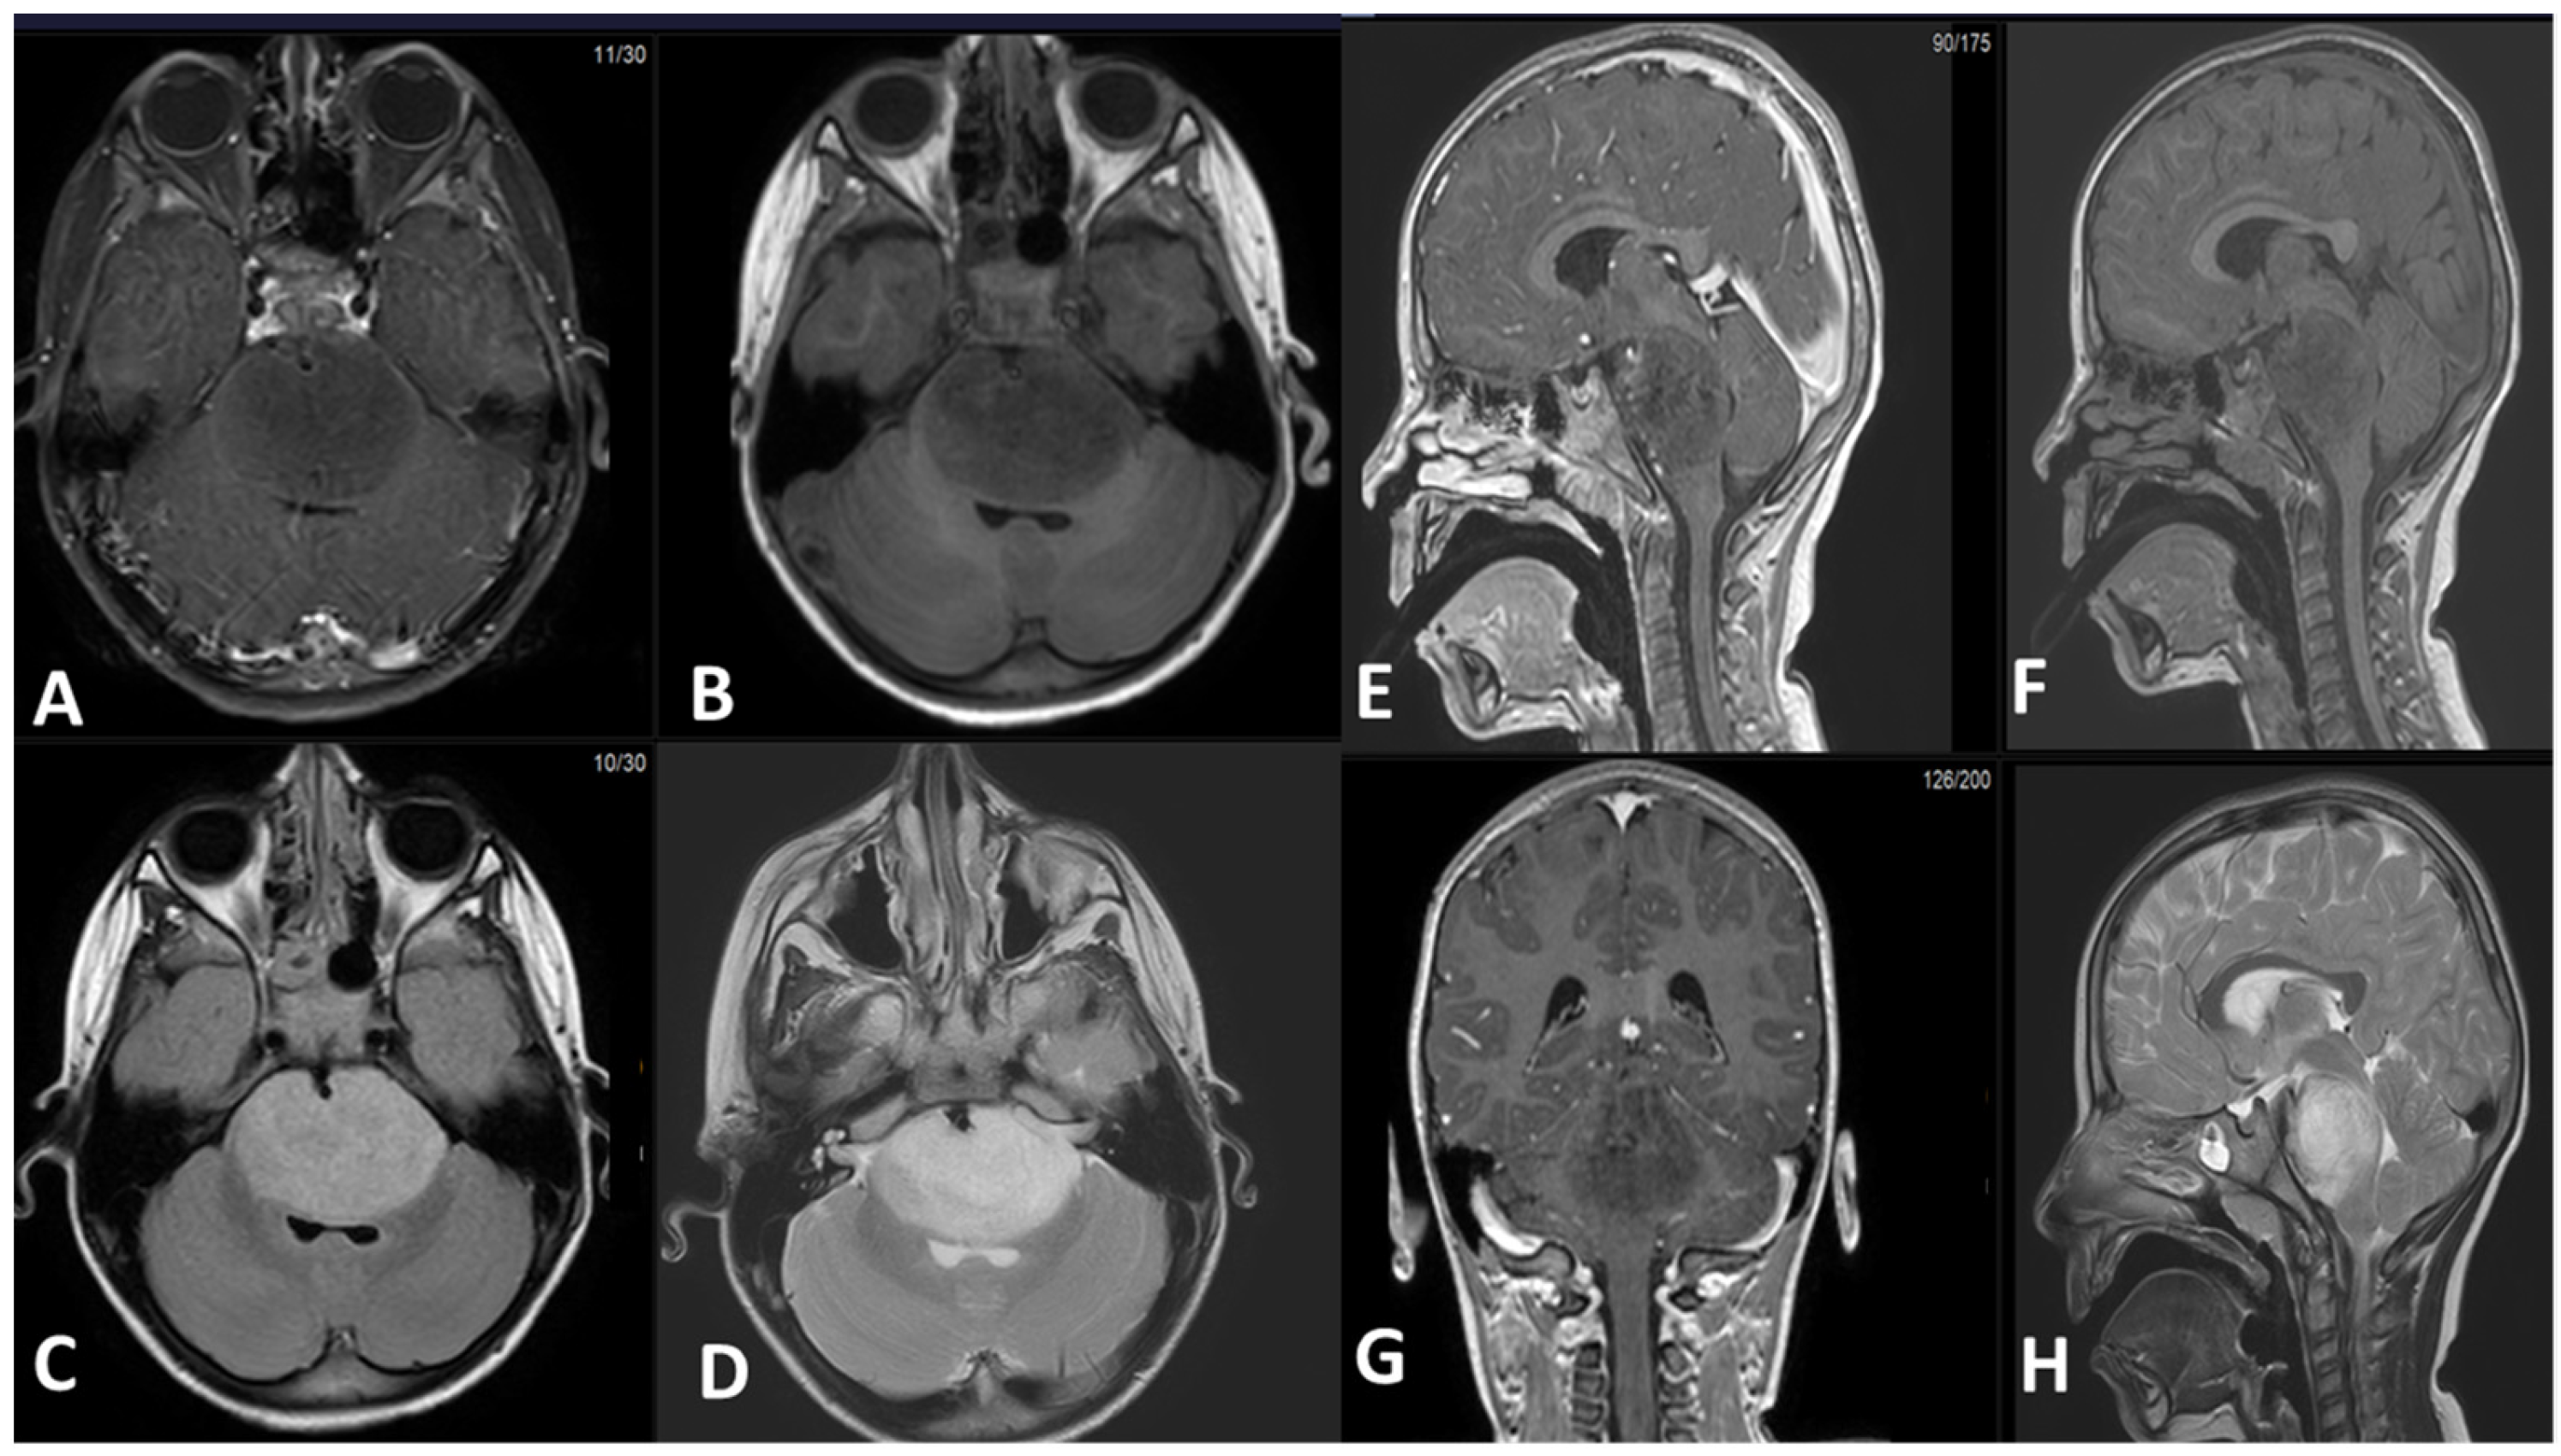

Figure 3 demonstrates an example of DMG arising from the pons. There is an expansible mass involving the brainstem, centered in the pons, obliterating the prepontine cistern and encasing the basilar artery. The mass shows hypointense signal on T1-weighted sequence, hyperintense signal on T2 and FLAIR sequences, and is non-contrast enhancing. It compresses the fourth ventricle. There is no proximal ventricular dilatation in this patient. The sagittal and coronal images show the proximal and distal extension of the mass to the pontomesencephalic and pontomedullary junctions, showing a somewhat indistinct border.

Figure 3.

(A) Axial T1-weighted post IV contrast fat saturated sequence. (B) Axial T1-weighted pre-IV contrast sequence. (C) Axial FLAIR sequence post IV contrast. (D) Axial T2 TSE sequence. (E) Sagittal T1-weighted post IV contrast sequence. (F) Sagittal T1-weighted pre-IV contrast sequence. (G) Coronal T1-weighted post IV contrast sequence. (H) Sagittal T2 TSE sequence. FLAIR (fluid attenuation inversion recovery). TSE (turbo spin echo).